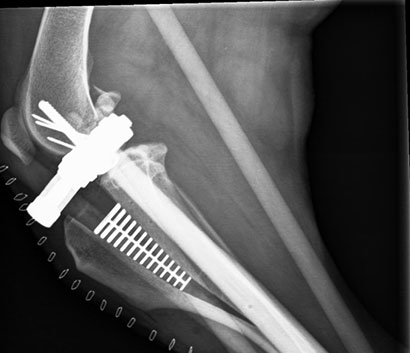

Da ihr Knie nach wie vor sehr instabil war, musste sie nochmals an den hinteren Kreuzbändern operiert werden.

Weiterhin werden wir jetzt versuchen, dass Knie mit gezieltem Muskelaufbau zu stabilisieren.

Dezember 2017

Auch der lästige Fixateur wurde inzwischen entfernt.

Dennoch- Ihre Klinikodysse ist noch nicht zu Ende.

Das Knie wurde, als man Laika überfuhr, stark geschädigt und es wird noch einiges Zeit in Anspruch nehmen bis es wieder richtig funktioniern wird.

Als nächste Operation steht das Kreuzband an. Anschliessend wird noch in der Klinik damit begonnen durch Bewegungstherapien Laikas Muskulatur zu stabiliseren.